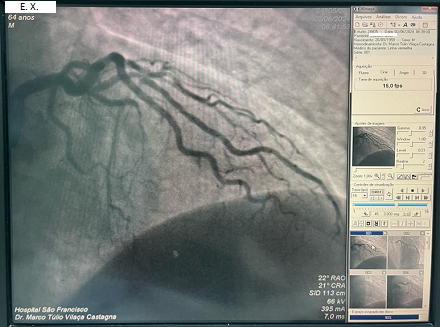

Methods: 70 consecutive patients were referred to coronary angiography (cath) due to typical chest pain and STEMI standard 12-lead ECG tracing. At cathlab, 4-electrodes-12-leads-wearable-smartphone-based-ECG-System(AngelUS®) tracing was performed. ECG tracings interpretations were compared between the 2 groups by independent cardiologists blinded to ECGs and then correlated with cath findings. The Cohen κ statistic was used to measure agreement between the 2 groups.

Results: Both cardiologists agreed to include 70 standard ECG tracing and 70 AngelUS® ECG tracing as STEMI. Both cardiologists agreed to exclude 70 standard ECG tracing and 70 AngelUS® ECG tracing as absence of STEMI, showing a perfect agreement with Cohen’s k:1. Correlations with coronary angiography were also performed showing total agreement with both ECG diagnostics.

Conclusion: In 70 consecutive patients with typical symptoms and STEMI, standard ECG and the AngelUS®4-Electrodes-12-Leads-Wearable-Smartphone-Based-ECG showed clinical agreement. Correlations with coronary angiography were also performed, showing clinical equivalence between both ECG diagnostics. Analysis of AngelUS® ECG tracing compared to standard ECG is ongoing, extending our investigation into the utility of this technology in preoperative ECGs.